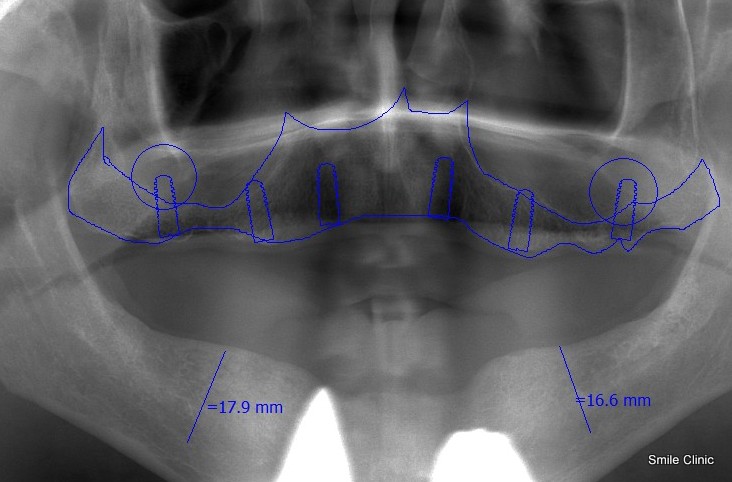

What happens when we do an x-ray and see this? (see the x-ray on the left)

Well, usually it’s time to get a set of false choppers, and put them in a glass by your bed each night – you know that you’ve passed that special stage in life – and it’s often very depressing.

People with no teeth left at all are called “edentulous” by dentists. The problems is, the longer some one wears dentures – the jawbone recedes even more and the face sinks.